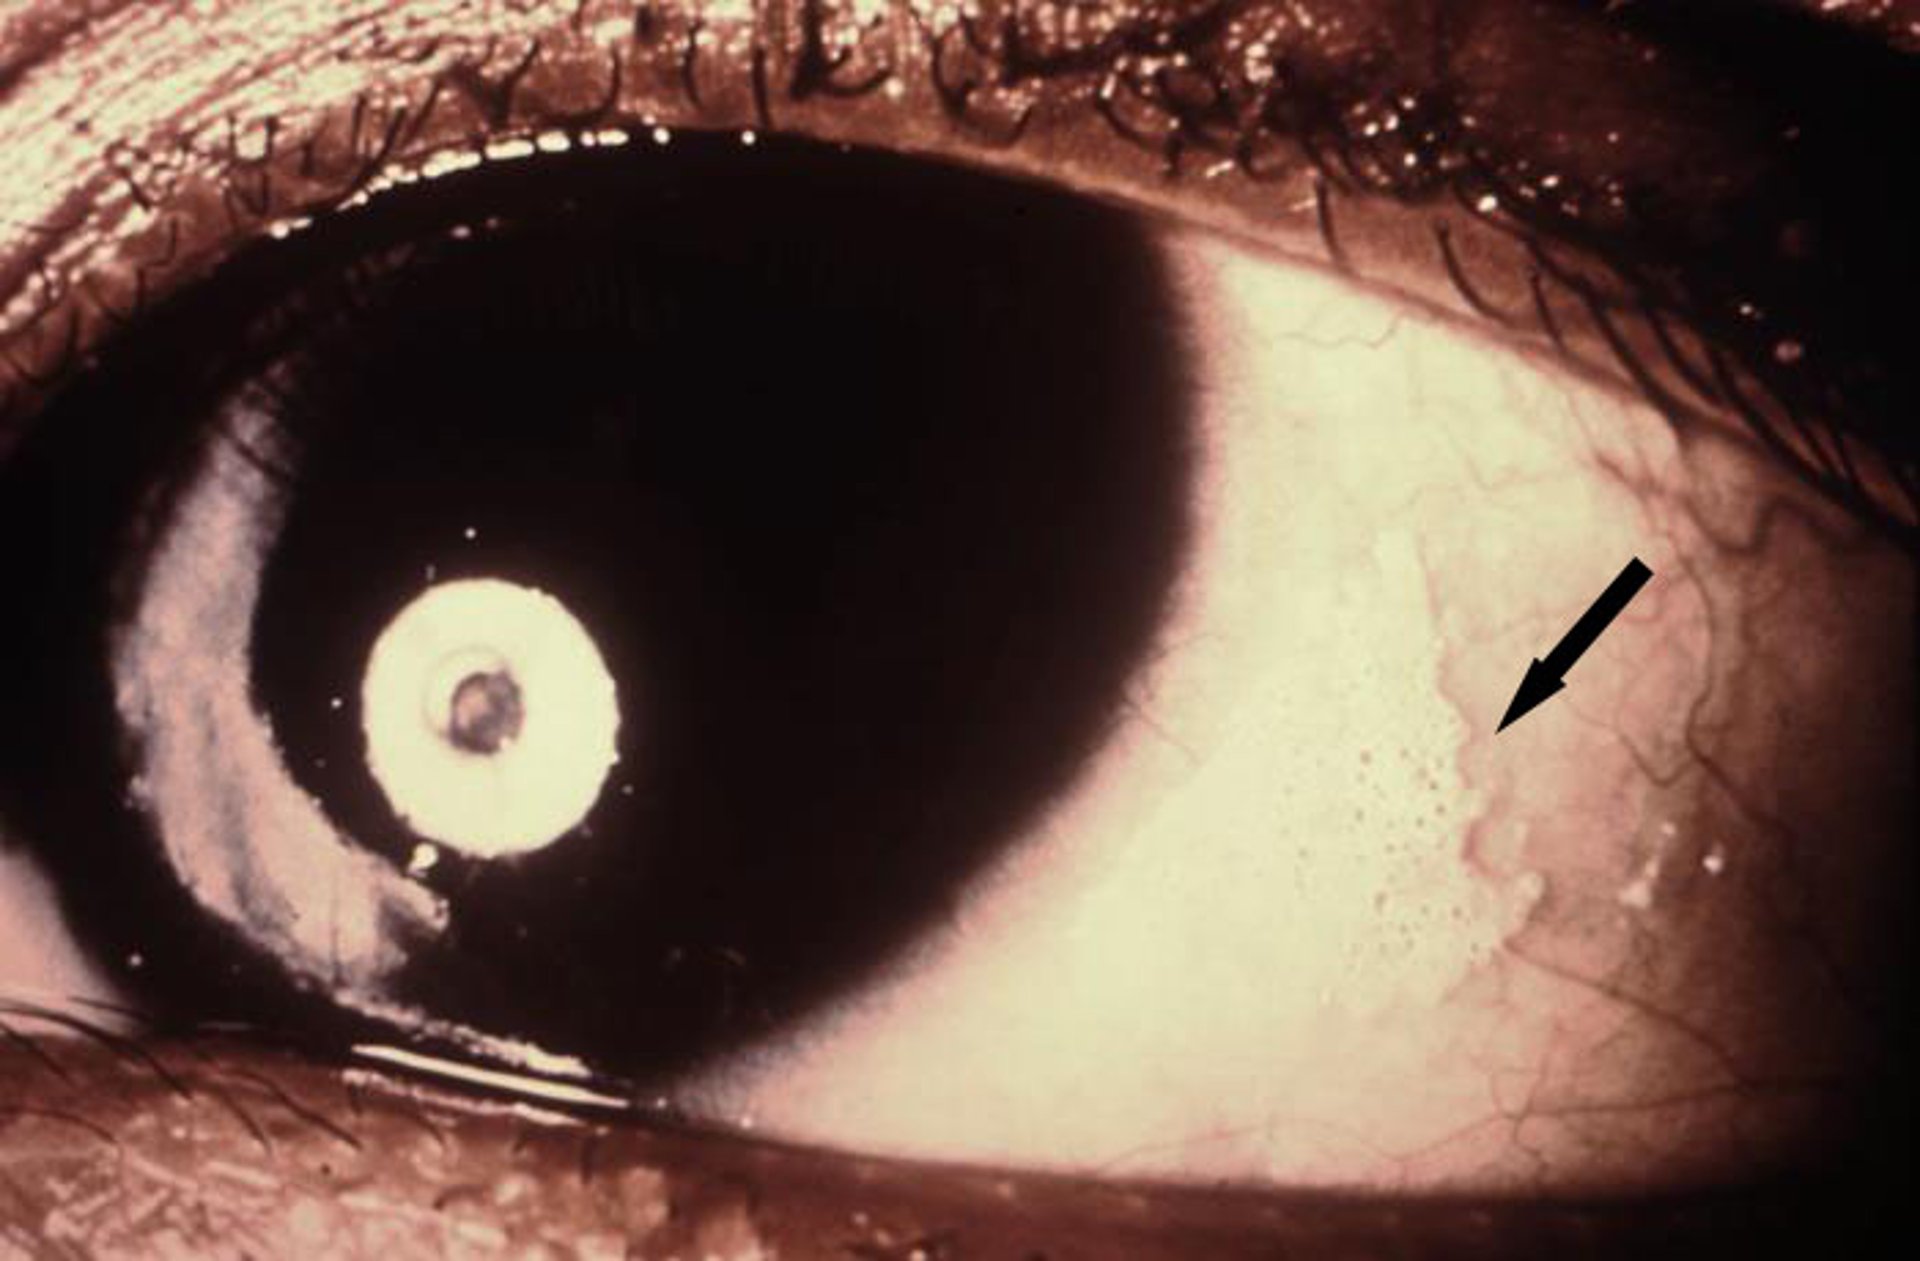

Esta foto mostra secura crônica da membrana conjuntival com manchas queratinizadas conhecidas como manchas de Bitot (seta).

Photo courtesy of the Nutrition Program via the Public Health Image Library of the Centers for Disease Control and Prevention.

Adaptação prejudicada dos olhos ao escuro, que pode causar cegueira noturna, é um sinal precoce de deficiência de vitamina A. Xeroftalmia (quase sempre patognomônica) resulta da queratinização dos olhos. Envolve secura (xerose) e espessamento das conjuntivas e córneas. Desenvolvem-se manchas espumosas superficiais compostas por secreções e células epiteliais na conjuntiva exposta (manchas de Bitot). Em deficiências avançadas, as córneas tornam-se nebulosas e pode haver erosões, as quais podem provocar sua destruição (queratomalacia).